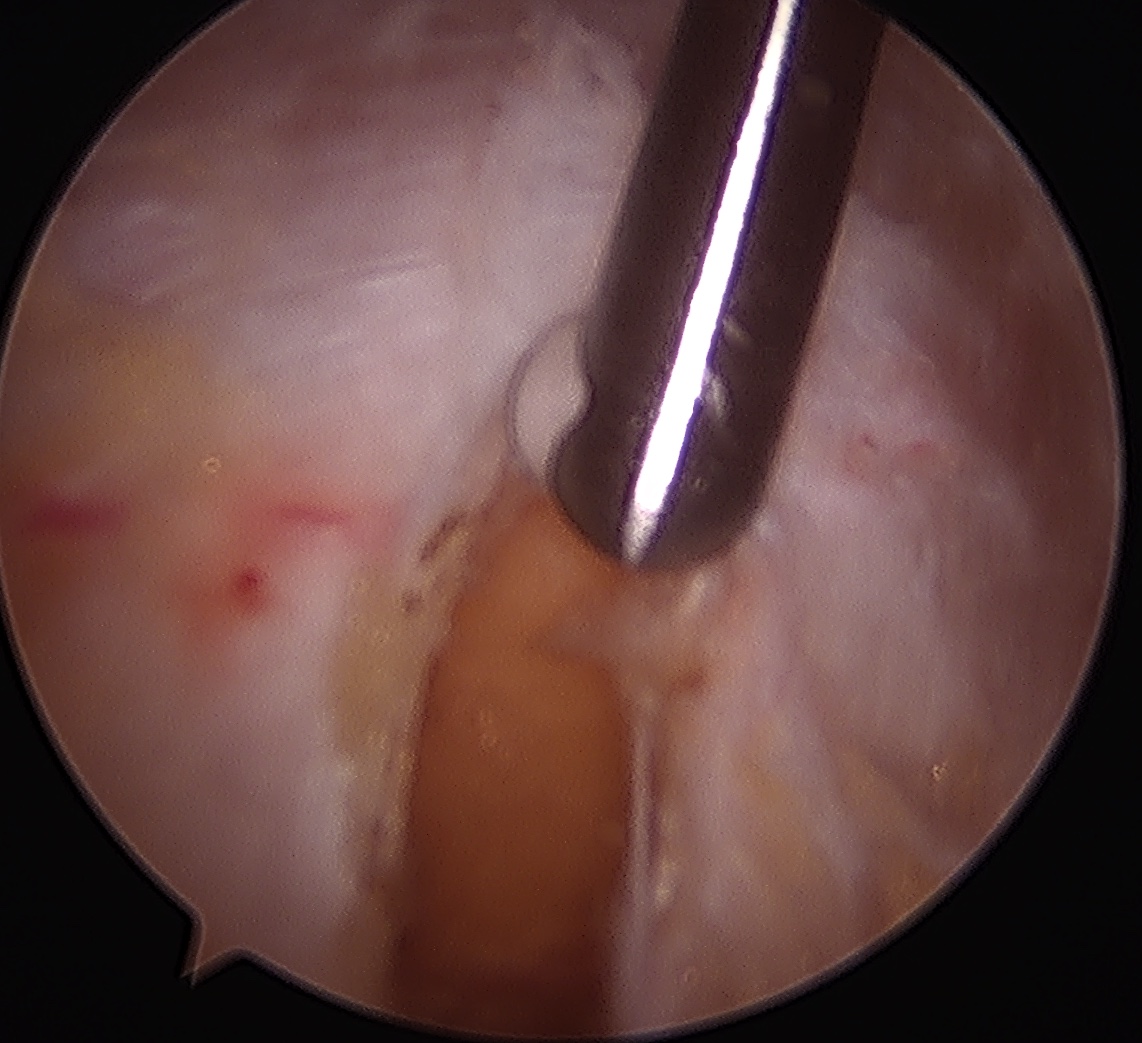

ITB vertical split / cruciform release + trochanteric bursectomy

ITB band Longitudinal split

Cruciform release anteriorly Bursectomy over abductors

Drummond et al Arch Orthop Traum Surg 2016

- endoscopic longitudinal ITB release with trochanteric bursectomy

- 49 patients mean age 60

- 20% not satisfied